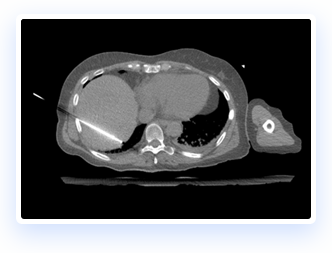

The IGTFusion System utilizes patented software algorithms to automatically align images from single and multiple image sources.

IGTFusion can visualize and register 3D image data from multiple modalities, including CT, PET, and MR images automatically.